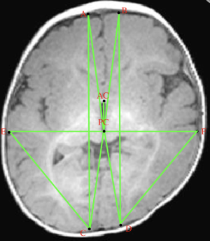

스크린샷 2026-01-26 08.45.34.png 뇌의 구조적 차이를 비교하기 위한 각종 랜드마크 표시

후두엽의 비대칭 및 형태 변형

이러한 결과들은 사두증에서 관찰되는 뇌 구조의 변화가 단순한 용적 감소보다는

형태와 배치의 차이에 가깝다는 점을 시사합니다.